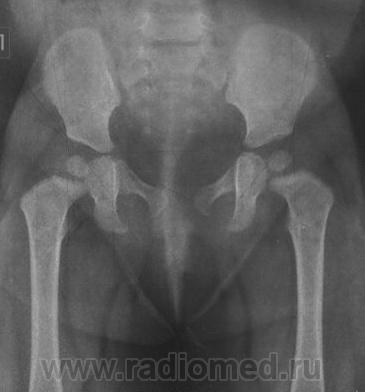

Это снимки моей дочери. На тот момент ей было 9,5 мес.

Объясните мне, пожалуйста, почему нам ставят диагонз дисплазия т/б суставов? Я не могу понять!

Заключение по этому снимку было таково:

-правая половина таза умеренно приподнята;

-ядра окостенения головок бедренных костей расположены в проекции ацетабулярной впадины, симметричны;

-ацетабулярный угол D=29гр, S=23гр;

-расстояние от центра вращения головок бедренных костей до линии Хильгенрейнера (h) D=S=10мм;

-угол наклона плоскости входа во впадину D=35гр, S=40гр;

-угол Виберга D=9гр, S=12гр;

-линии Шентона и Кальве не нарушены;

-симптом Омбреданна отрицательный с обеих сторон.

Заключение: На момент исследования определяются Rg-признаки дисплазии правого тазобедренного сустава.

думаю дело в укладке, а диагноза этого не бойтесь... вам же опрерироваться или какие то таблетки не предлагают.. а дисплазия это отклонение от официальной нормы, так сказать определенная группа риска, дажен не риска, а особого внимания...

Это норма.. извините за эмоции.